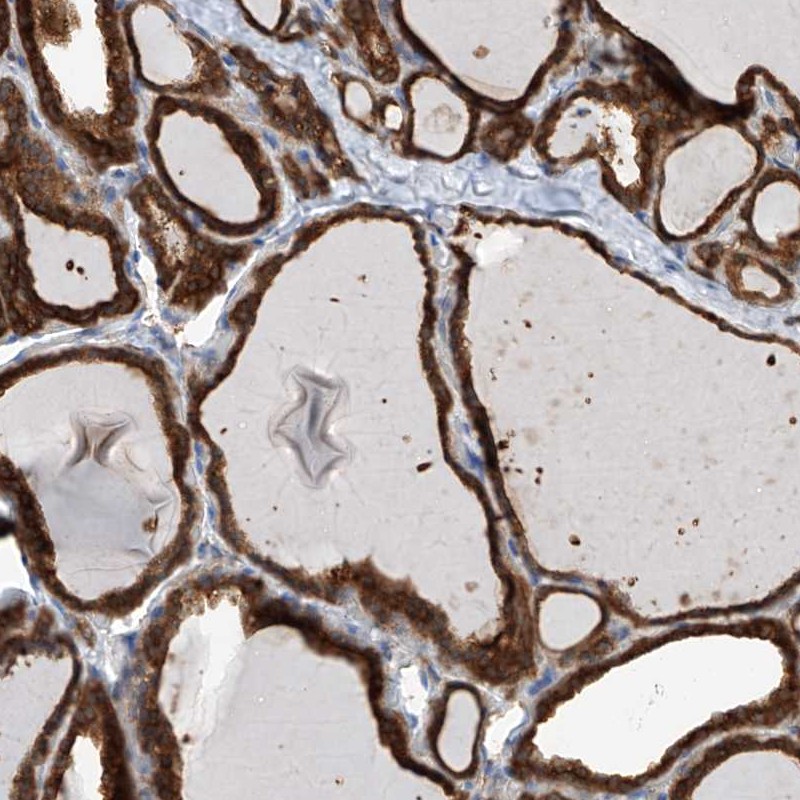

Immunohistochemical staining of human thyroid gland shows strong cytoplasmic positivity in glandular cells.